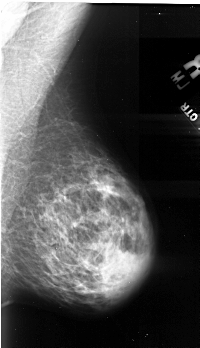

A_1103_1.LEFT_MLO

LEFT_MLO LINES 5191 PIXELS_PER_LINE 2986 BITS_PER_PIXEL 16 RESOLUTION 42 OVERLAY